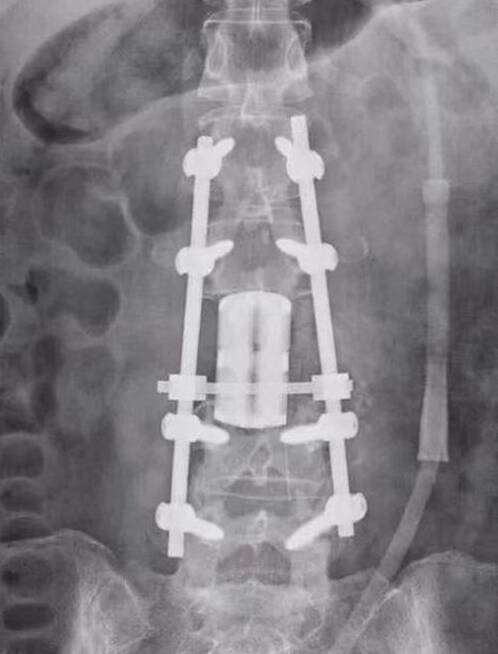

新疆醫(yī)科大學(xué)第三臨床醫(yī)學(xué)院完成3D打印人工椎體置換手術(shù)

今日,據(jù)魔猴網(wǎng)了解,新疆醫(yī)科大學(xué)第三臨床醫(yī)學(xué)院(附屬腫瘤醫(yī)院)骨與軟組織腫瘤及黑色素瘤科聯(lián)合麻醉與圍術(shù)期醫(yī)學(xué)中心、輸血科等多個(gè)學(xué)科,成功完成新疆首例3D打印人工椎體置換手術(shù)。

面對(duì)這樣一例高難度的手術(shù),江仁兵團(tuán)隊(duì)精心設(shè)計(jì)了后路-前路-再后路三階段手術(shù)的治療方案。3D打印的人工椎體具有組織相容性好、耐磨、壽命長(zhǎng)的特性。歷時(shí)10個(gè)小時(shí)手術(shù),3D打印人工椎體被成功植入單女士體內(nèi),放置位置精準(zhǔn),與周?chē)M織結(jié)構(gòu)契合牢固,手術(shù)順利完成。 3D打印人工椎體完美契合了上下正常椎體的連接面,其3D多孔鈦合金打印設(shè)計(jì)為人工椎體提供了足夠的生物力學(xué)強(qiáng)度,增加人工椎體的穩(wěn)定性。